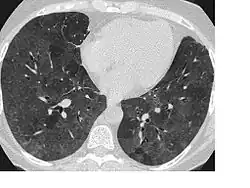

Signs and symptoms of flock worker's lung include rales (crackling noises caused by fluid in the lungs), dyspnea (shortness of breath), and coughing. Abnormalities seen on a computed tomography (CT) scan of the lungs can include ground glass opacity and reticular opacity. The typical histopathology in flock worker's lung is bronchiolocentric interstitial pneumonitis and lymphocytic bronchiolitis with lymphocytic hyperplasia. Occasionally, desquamative interstitial pneumonia and bronchiolitis obliterans organizing pneumonia can be seen.[3][4]

A CT scan of the lungs and histopathology along with a history of working in the flocking industry can diagnose flock worker's lung. A differential diagnosis may also include Sjögren's syndrome and lymphoid interstitial pneumonia.[3] Flock worker's lung may be misdiagnosed as asthma or recurrent pneumonia.[9] Though X-rays may be abnormal, CT scans are more useful as a diagnostic tool in flock worker's lung.[5] Other diagnostic methods may include a transbronchial biopsy or wedge biopsy.[9]